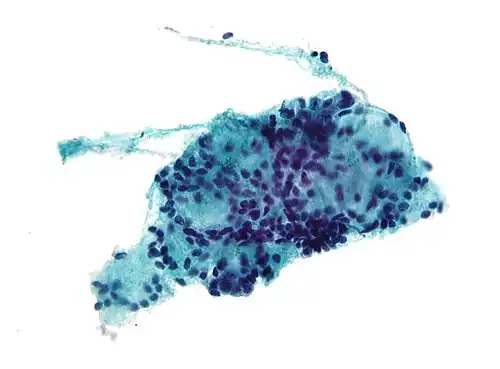

![]() Micrograph of a needle aspiration biopsy specimen of a salivary gland showing adenoid cystic carcinoma. Pap stain. | |